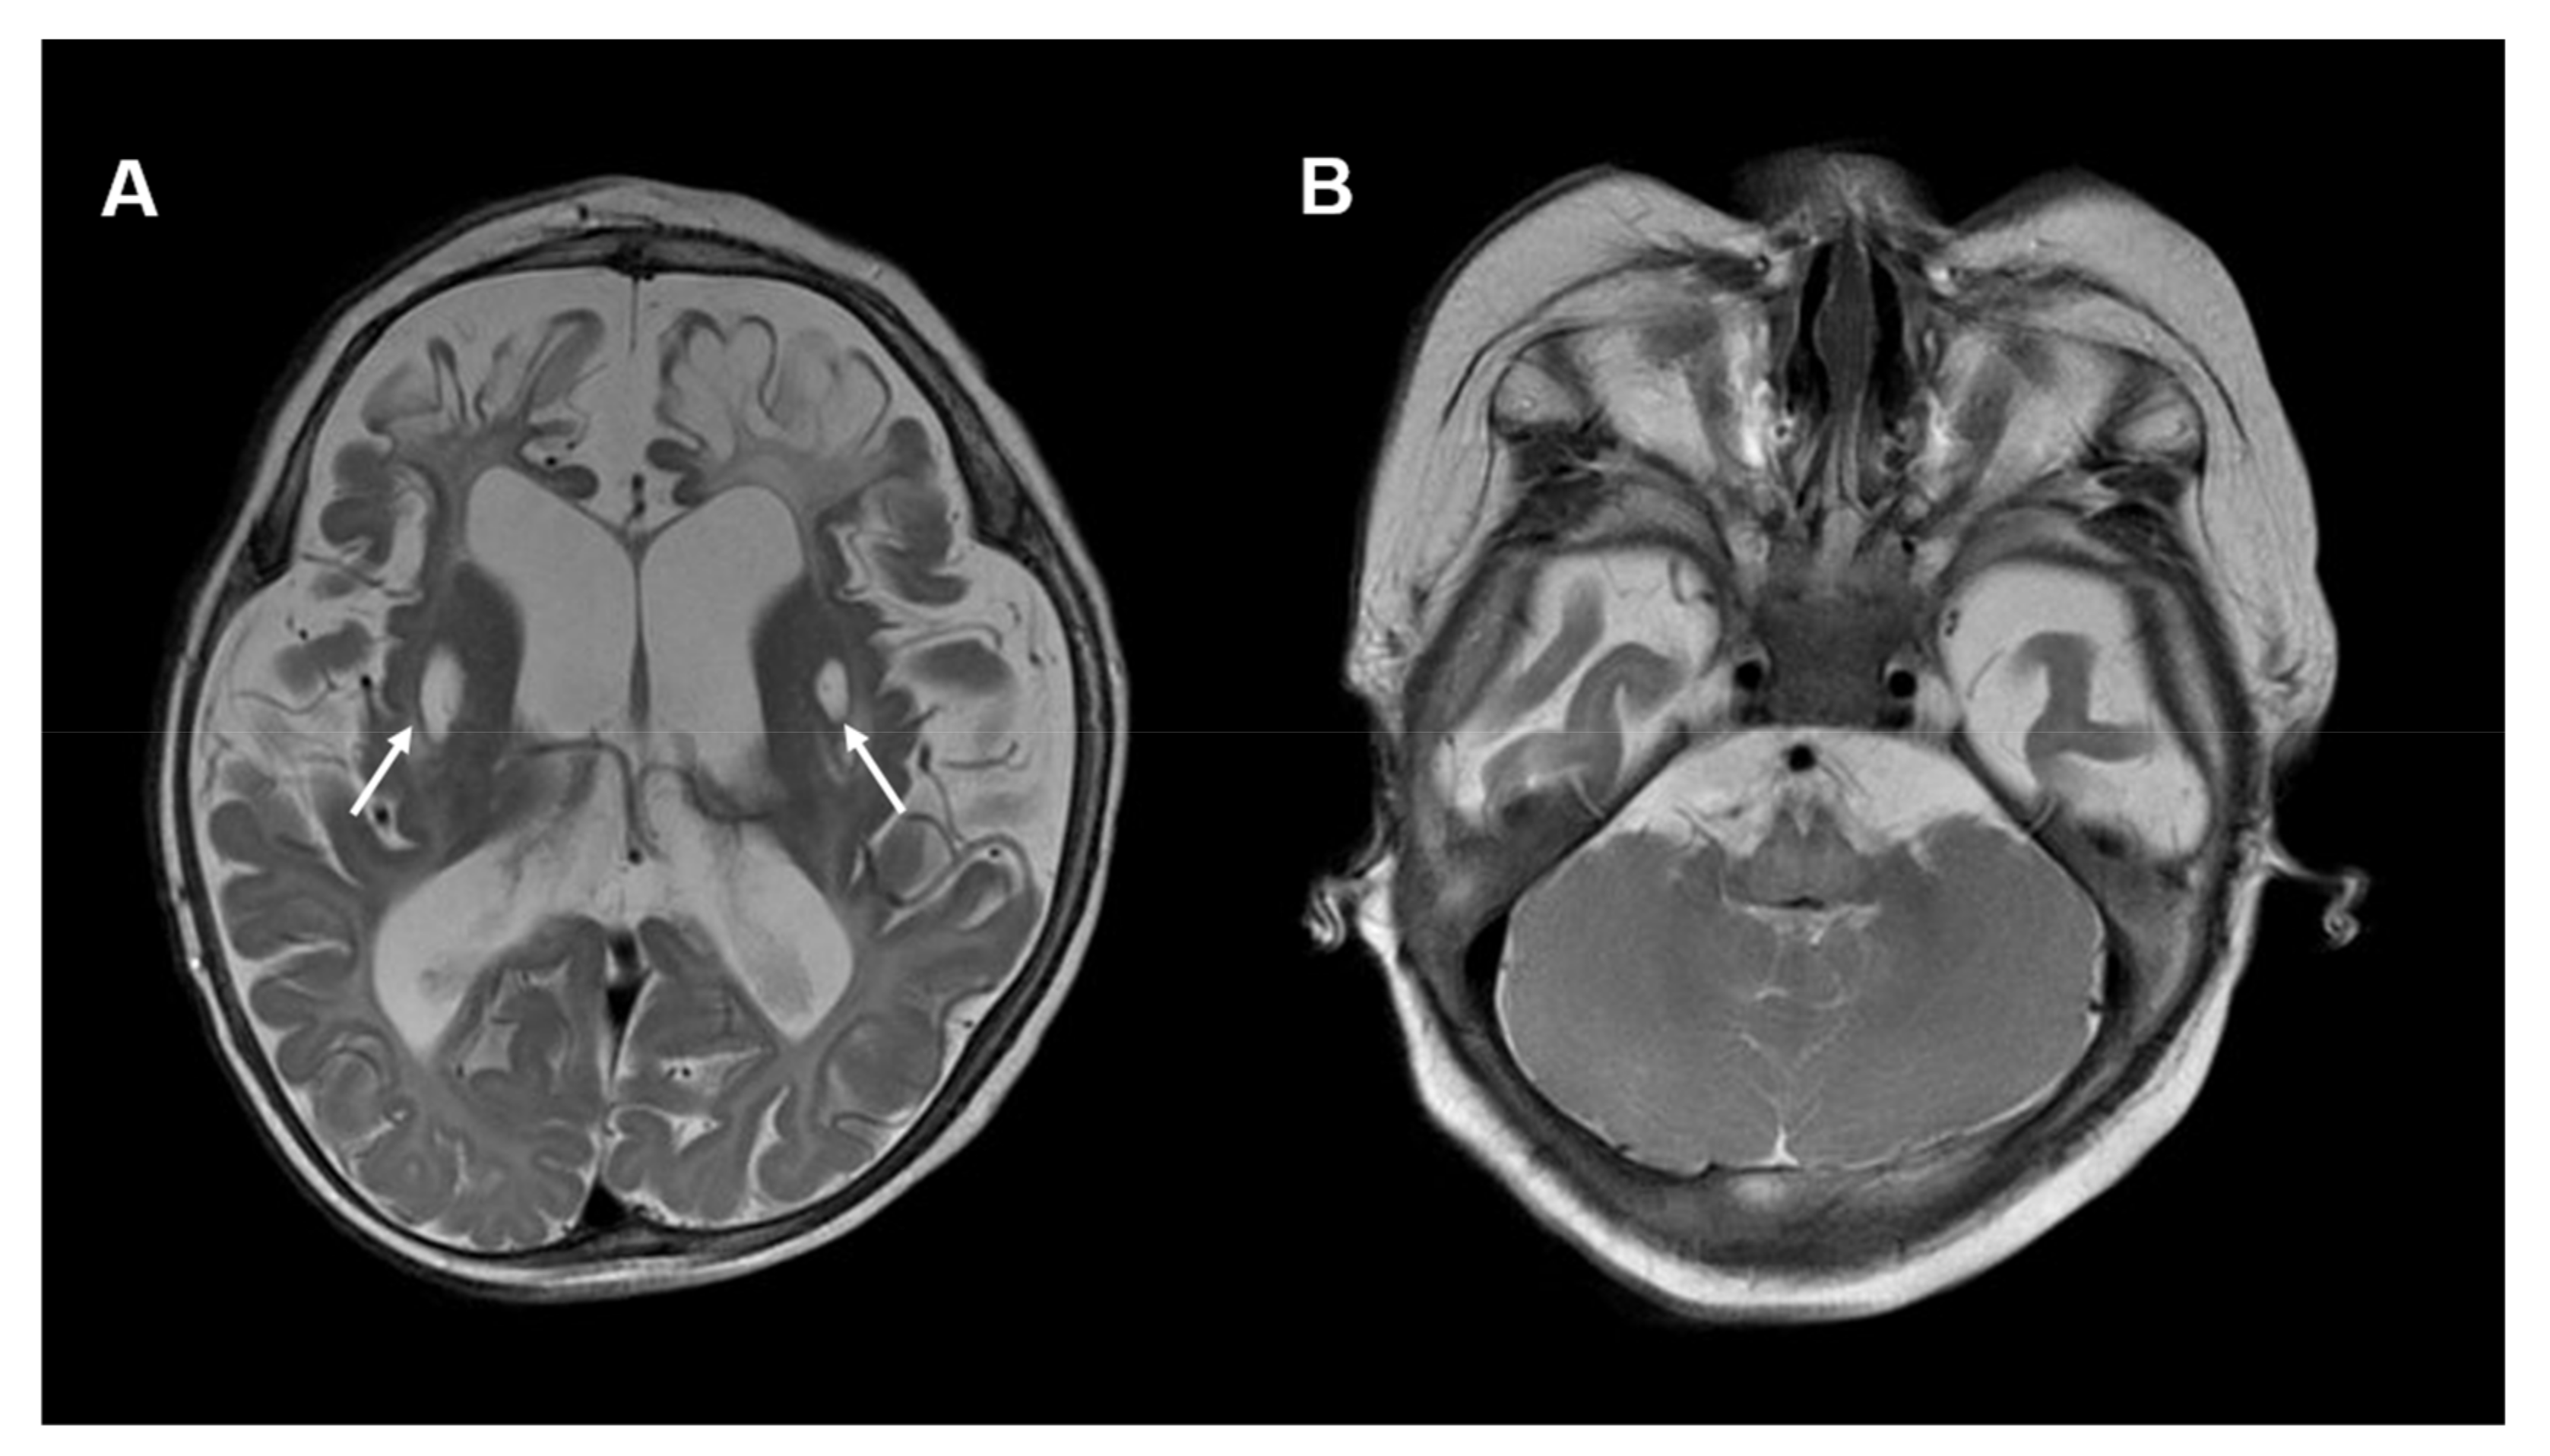

In addition to the reported individuals, we recently identified an infant with HPDL deficiency (not yet published). The girl presented with seizures, global developmental delay and microcephaly at the age of 3 months. The brain MRI showed subcortical T2-hyperintense lesions predominantly in the right frontal region (see Figure 6). Moreover, bilateral thalamic lesions were seen. MR spectroscopy did not reveal clear abnormalities.

Figure 6.

Neuroimaging in HPDL deficiency: (A) Brain MRI, T2-weighted images of a 3-month-old girl with HPDL deficiency. Images show subcortical T2-hyperintensities, mainly affecting the right frontotemporal regions. Moreover, asymmetrical signal abnormalities of the thalami are visible (white arrows). (B) No cerebellar abnormalities are visible.